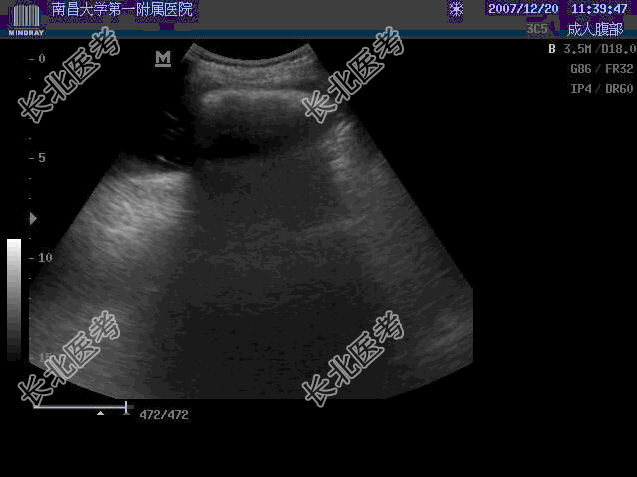

- 单项选择题患者,男, 17岁,消廋 , 发现腹部包块2个月,来院检查.超声发现: 上腹部内见到一8.8cm×5.6cm强光团,后伴明显声影, 并可随探头挤压而移动,患者饮水800ml后, 并取站立位,发现该光团位于胃腔内, 且随重力作用而降至脐水平以下2cm。追问病史,患者于2个多月前吃过2次柿子, 且量比较多。超声声像图如图,应诊断为